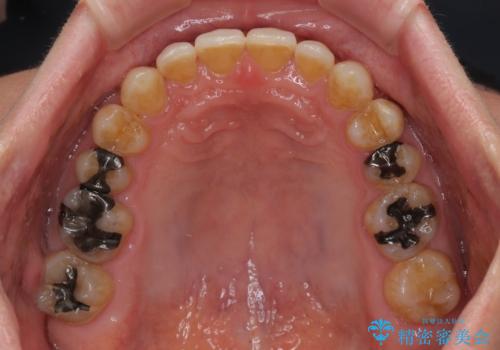

ディープバイトが改善され、睡眠時の食いしばりも緩和され、顎への負担が軽減されました。

手前に傾斜している奥歯をワイヤー装置で立ち上がらせ、咬み合わせの高さを挙上することで突き上げを解消し、空隙歯列を改善していくこととしました。